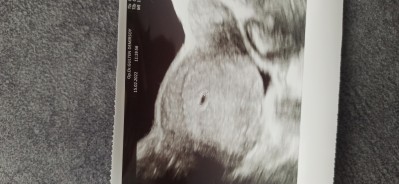

Kizlar arkadasim 2.600 kan sonucu ile keseyi goremedi sizler kacla gormustunuz bu durum normal mi

7700 küsurde gördük biz keseyi

Çok erken sizinki daha. Birde betayla da pek alakası yok sanırım düzenli artıyorsa

3000 den Sonra görünür tabi makinanın kalitesi de önemli

Ben 4554 görmüstüm keseyi

1504 de gördüm keseyi

Doktor 3000 den sonra görcez demişti bir hafta sonra gittim 8203 de keseyi gördüm

1640 nokta kadar da olsa göründü